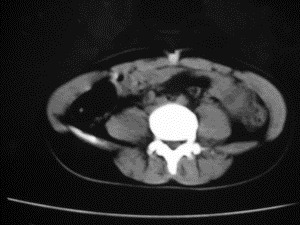

患者女,20岁,被车撞伤3小时,pe:全腹肌紧张,压痛反跳痛,以右上腹为著,肠鸣音减弱。有手术结果。![]() ![]() ![]() ![]() ![]() ![]() ![]() ![]() ![]() ![]() ![]() ![]() ![]() ![]() ![]() ![]() ![]() ![]() ![]() ![]() ![]() jiajie发言: ![]() 考虑空腔脏器穿孔。 dyqct发言:考虑:1、肝左叶外侧段断裂伤伴少量腹血。2、空腔脏器穿孔。 fangzheng发言:仅见腹腔内游离气体,提示空腔脏器穿孔。 guoke发言:胃内密度增高,肠腔内充满气体,考虑肠腔破裂出血 mmg94发言:胃后壁见一增厚软组织密度影,肝左叶前见游离气体影,左腹腔内局部肠管壁、系膜增厚。并见类圆形软组织。以上征象提示消化道管腔破裂,小肠、肠系膜挫裂伤,腹腔血肿形成。 拾荒者发言:肝实质密度不均匀,胃内见不均匀高密度影。考虑:肝挫裂伤,胃内应激性溃疡出血。 守望可可西里发言: 以下是引用jiajie在2006-6-20 15:49:00的发言:[br] [br][br]考虑空腔脏器穿孔。jiajie老师,我鼓起了很大的勇气才决定给您唱个反调儿,如果我错了,请您一定给我指出来,谢谢您了。我反复看了解剖图谱,觉得您所说的“考虑空腔脏器穿孔”上图所用箭头标明的不是游离气体。请您看以下几幅图片: ![]() ![]() ![]() ![]() ![]() ![]() ![]() ![]() 再请您看向医生老师发表的解剖图谱3幅 ![]() ![]() ![]() 这以下几幅图,我认为是肝包膜下积血。不过,说实在话,我没有发现有明显的肝挫裂伤。不对的地方请您一定指出来,再次感谢您了,jiajie 老师! ![]() ![]() ![]() ![]() 这下面几幅图片,我认为有明显的左中上腹部小肠损伤。 ![]() ![]() ![]() ![]() ![]() ![]() ![]() ![]() jiajie 老师,估计我说的是错误的,但我实在闹不明白,请您一定不要笑话我,并指出我的错误,以便于我减少工作中的失误。再次感谢您了,jiajie 老师! 至于胃内的不均匀高密度,我认为拾荒者战友说的有道理,胃内应激性溃疡出血和胃内容物混合所致。 手术结果:左肝叶(iv段)前缘长约8cm挫裂伤口,舌叶根部下< |